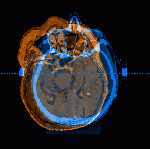

CT scan